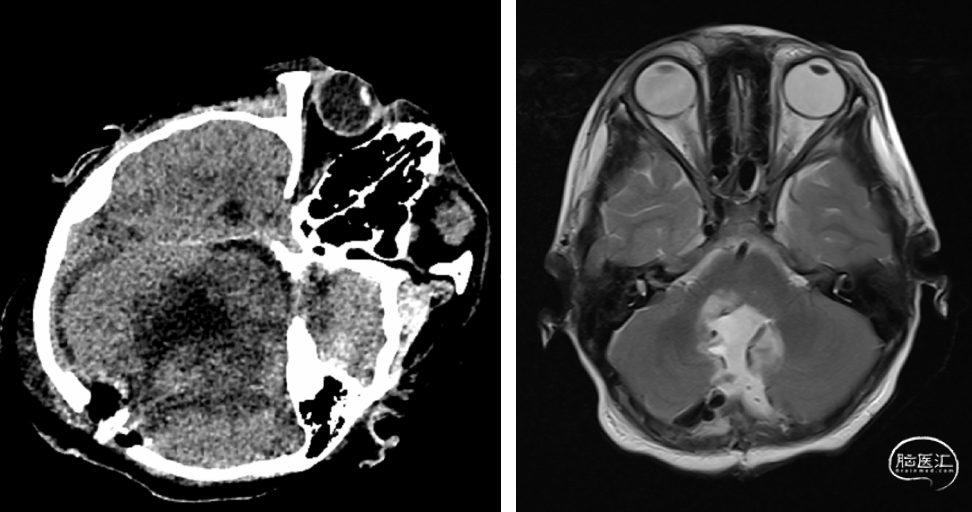

入院后完善各项术前准备,头部增强MRI提示第四脑室类圆形病变,大小约37.2mm×41.8mm×41.7mm(左右×前后×上下),呈长T1长T2信号,内部少许结节状混杂信号,增强扫描呈不均匀轻度强化,内见迂曲增宽血管影,脑干受压,幕上脑室系统扩张(图1)。

图1. 术前头颅MRI提示第四脑室类圆形病变,大小约37.2mm×41.8mm×41.7mm(左右×前后×上下),呈长T1长T2信号,内部少许结节状混杂信号,增强扫描呈不均匀轻度强化。